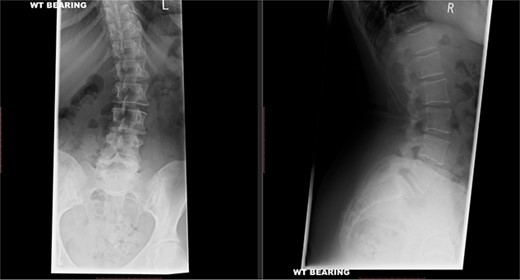

X-rays of the lumbar spine (Fig. 1) and pelvis performed in December 2015 showed a small idiopathic scoliosis in the lumbar spine. A magnetic resonance imaging (MRI) scan was performed in February 2016, which showed non-compressive disc degeneration and disc bulge at L4/5 and L5/S1. She was referred to physiotherapy for rehabilitation.

Preoperative X-ray of the lumbar spine performed in December 2015, confirming small idiopathic scoliosis in the lumbar spine.